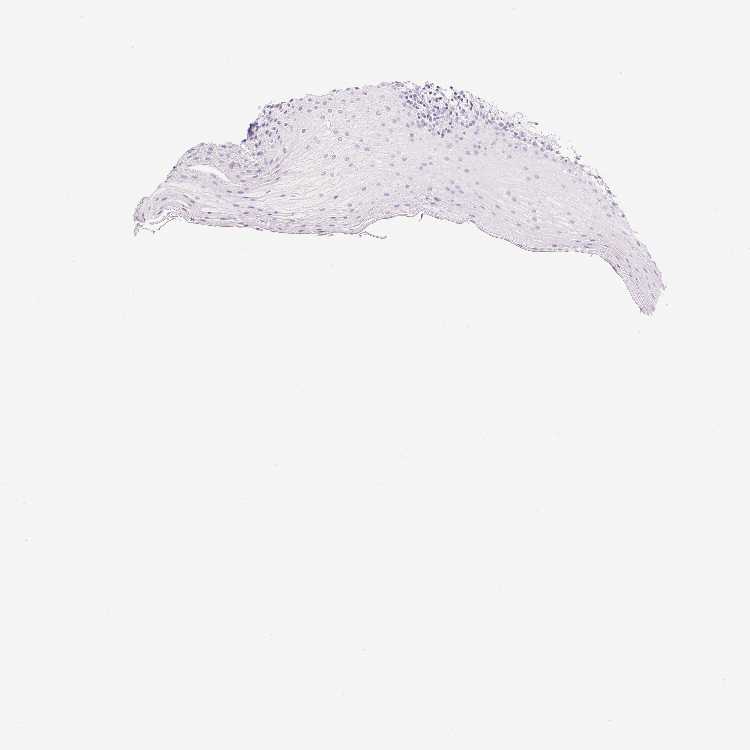

TISSUE PRIMARY DATA ORAL MUCOSA Show tissue menu

ORAL MUCOSA - Antibody stainingi

Antibody staining in the annotated cell types in the current human tissue is reported as not detected, low, medium, or high, based on conventional immunohistochemistry profiling in selected tissues. This score is based on the combination of the staining intensity and fraction of stained cells. Each image is clickable and will lead to virtual microscopy that enables deeper exploration of all samples and also displays staining intensity scores, fraction scores and subcellular localization as well as patient and tissue information for each sample.

Antibody HPA046834

Squamous epithelial cells Not detected